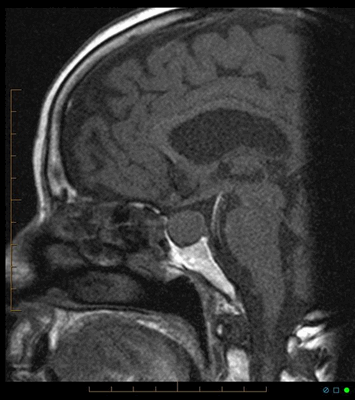

В норме воронка гипофиза должна располагаться на срединной линии, а сама железа - иметь однородную структуру и близкую к прямоугольной форму. Его нижний край должен напоминать изгиб турецкого седла, а верхний может быть выпуклым, прямым или вогнутым. На фронтальной проекции его части должны быть симметричны, но легкие отклонения не считаются патологией.

МРТ гипофиза в норме

Нормальные размеры гипофиза на МРТ

Нормальные размеры, масса и объем гипофиза на МРТ коррелируют с полом, возрастом. У беременных допускается увеличение питуитарной железы, но после родоразрешения в течение 6 месяцев параметры возвращаются к среднестатистическим.